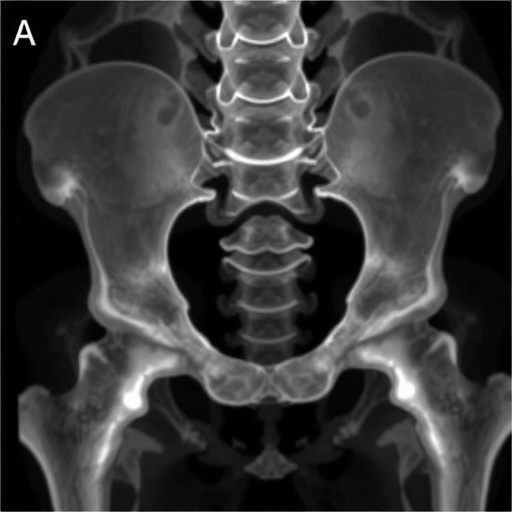

Technologically, this study harnesses cutting-edge imaging modalities like 3D computed tomography scans and digital segmentation tools, which allow for unprecedented visualizations and measurements of complex pelvic anatomy. The digital morphometric approach surpasses traditional manual measurements by reducing observer bias and improving reproducibility—essential qualities in forensic science where standardization is paramount.